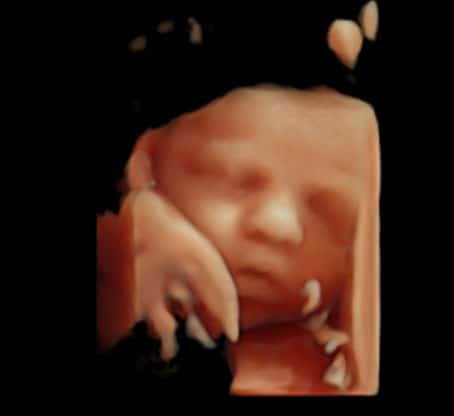

2. L’échographie du 1er trimestre (12 à 13 SA – 2 mois1/2)

Cette échographie, aussi appelée échographie de dépistage du 1er trimestre, est un examen complet du fœtus et du début de la grossesse.

Elle permet :

• De vérifier la vitalité du fœtus

• De contrôler la croissance et la morphologie précoce

• De mesurer la clarté nucale, un paramètre utilisé dans le dépistage de la trisomie 21

• De dater la grossesse avec précision si ce n’était pas encore fait

• D’observer le placenta, le cordon et les annexes

C’est un moment riche en émotions : votre bébé bouge déjà beaucoup et prend peu à peu une apparence humaine.